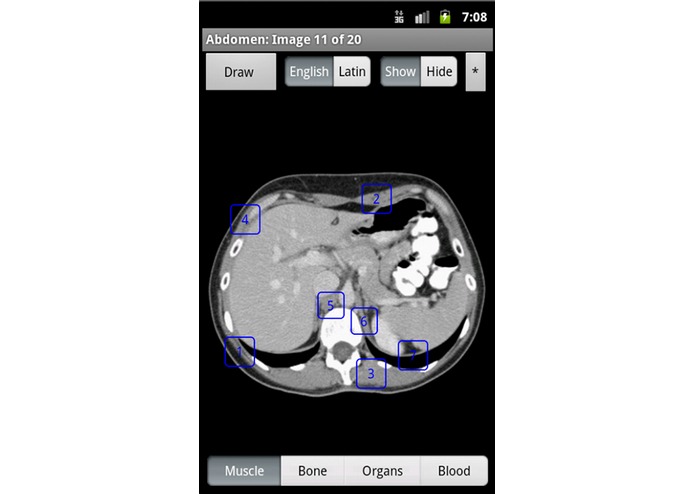

Learning anatomy interactively with a touchscreen device is dynamic and engaging. Having it as an app, makes the information available anywhere, anytime. Using the Samsung Pen, doctors can go over anatomy with patients, annotate normal anatomy images, and send the patient an email of the annotated image. This is a revolutionary way to increase doctor patient communication. iAnatomy is an exciting electronic anatomy atlas. The images are interactive. If a label is touched, the name of the structure is shown. Images span from the face to the pelvis. The face and neck images and the female pelvis images are reconstructed from data from the National Library of Medicine's Visible Human ProjectⓇ. iAnatomy is designed to stand on its own and does not require an ongoing internet connection. Anatomy labels can be hidden or shown. Anatomy can be viewed with either English or Latin medical terminology. A 'Draw' option allows the user to take an image, annotate it and mark it up and then save and/or email the annotated image. This is useful for healthcare workers using the image annotation to explain relevant anatomy and pathology to their patients. They can then email the image with their notations to the patient. This will help improve communication between patients and healthcare workers and is a useful tool for patient education.

iAnatomy helps students from middle school through medical school learn anatomy in a fun, organized way. You first choose the body part you want to study, then pick the category of anatomy labels to be displayed. The labels are divided into Muscle, Bone, Organs, or Blood categories in order to focus learning and limit the number of labels on the image at any one time.